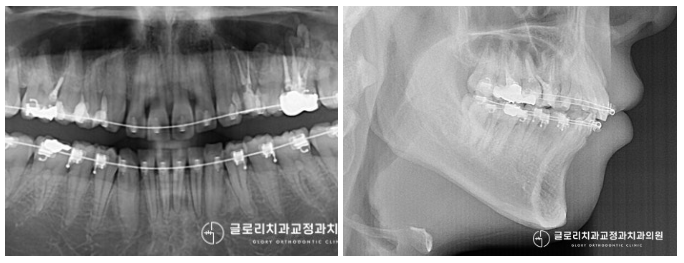

준비한 예시 자료를 확인해 보면

왼쪽 중절치가 우측으로 틀어져

삐뚤어져 있는 모습이 관찰됩니다.

전체적으로 돌출감도 함께 동반되었는데요.

문제는 여기서 끝이 아니었습니다.

초기에 배열 공간이 부족해서 그런지..

이전 치료 시 치간 삭제를 너무 많이 하여

곳곳에 여유 공간이 남아있는데요.

음식 찌꺼기가 자주 끼었을 것으로 보이네요.

악궁 또한 V-shape을 갖고 있었으며,

안모를 확인해 보면 약간 무턱에 가까운

모습을 갖고 있습니다.

발치나 치간 삭제 없이

돌출 및 총생 개선을 진행하고 있는 모습입니다.

이전에 문제가 되었던 중절치도

제자리를 찾아 고르게 배열되어 있으며

다른 치아들도 긴밀한 교합을 갖게 되었는데요.

전체적으로 봤을 때 훨씬 심미적이고

안정적인 모습을 갖게 되었습니다.

구치부 또한 1치대 2치로 잘 맞고 있었으며

악궁도 V에 가까운 치료 전 모습에서

둥근 U자로 바뀐 것을 확인할 수 있습니다.

골격적인 문제를 개선한 건 아니지만,

상악 돌출이 개선되어 이전에 비해

훨씬 세련된 입매로 바뀌었네요^^